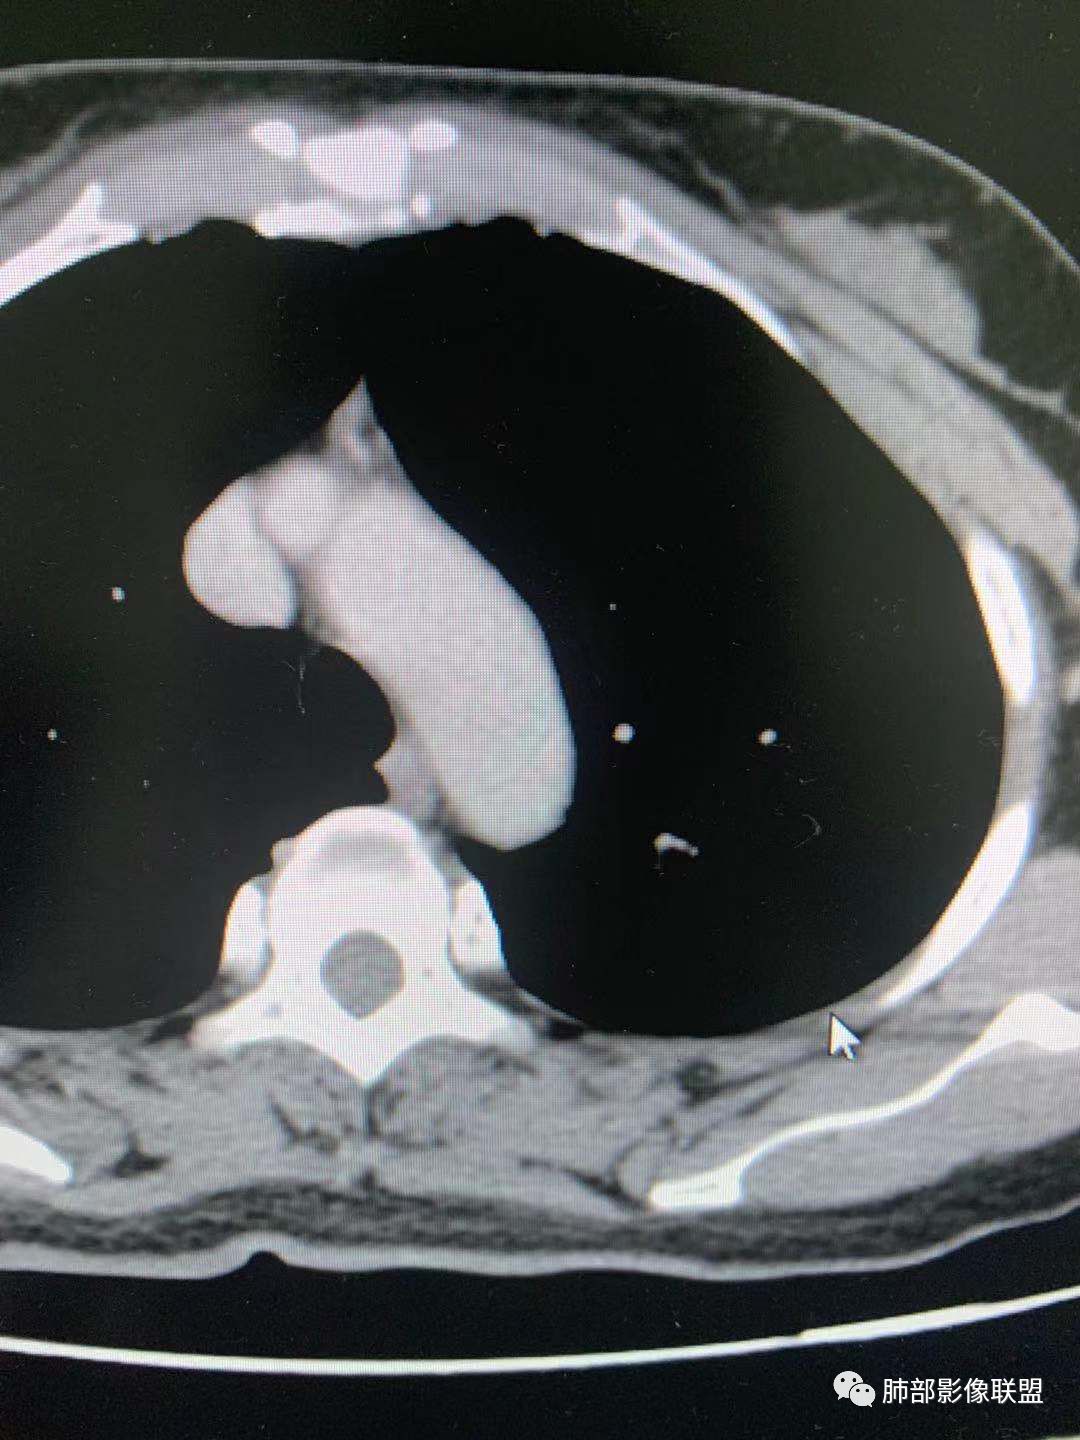

一.尖后段高密度大结节:

1.左肺上叶尖后段较大类圆形实性密度结节影,密度均匀,中等程度强化。

2.实性密度区边缘相当清楚,表面欠光整,偶见毛刺、棘突和旁出血管结构,未见典型的深分叶及邻近胸膜凹陷。

3.可疑支气管进入受阻。可惜缺乏连贯图像或冠矢状位以资判断。

4.病灶与胸膜之间有连线,邻近段支气管及肺血管整体后移,提示病灶还是有一定收缩性。

如上,单就这实性结节,硬化性肺细胞瘤(PSP)和腺癌似乎都能够解释,形态太规整了一些。

5.病灶周围见边界清楚的磨玻璃影,有点醒目,有点意外!

这是无论如何不能忽视的征象!

这点强烈提示,要么整个病灶恶性(腺癌),要么良性病灶旁滋生恶性病灶。

两年前左上肺的病灶什么位置,什么模样,是否相关?我们不得而知。